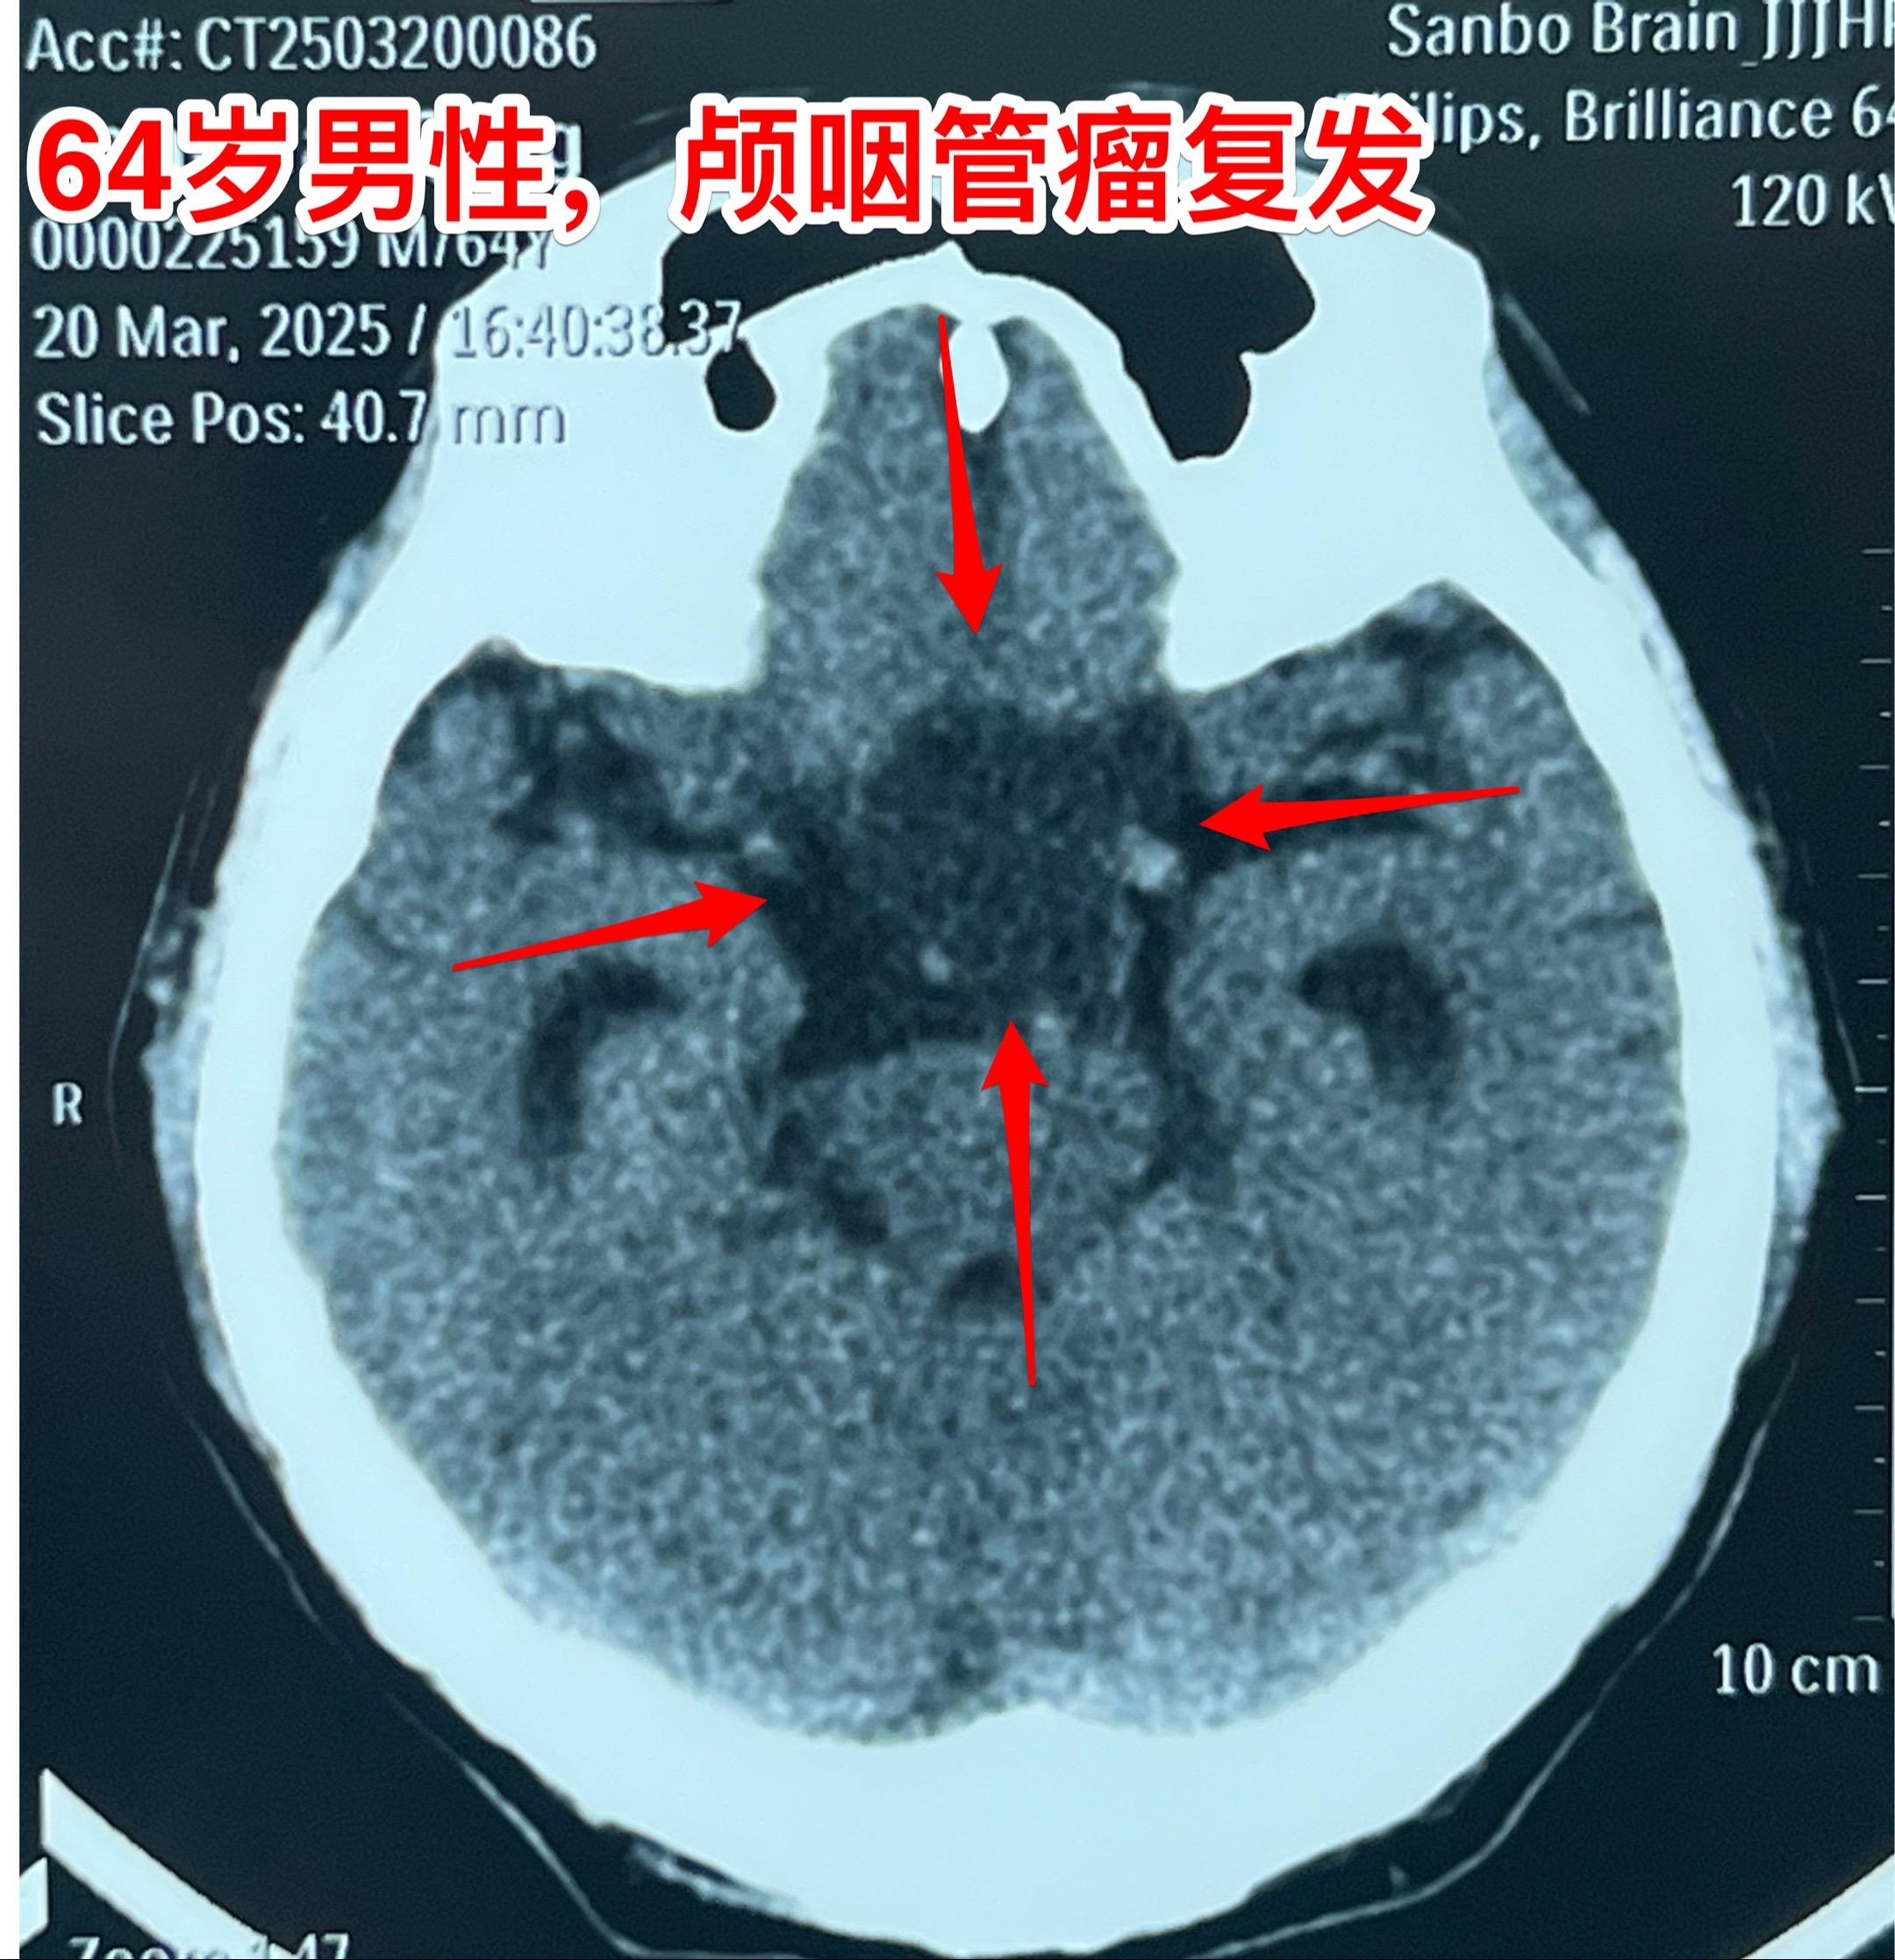

3月28日两个颅咽管瘤手术 两个都是经鼻手术手术后复发的颅咽管瘤手术。我采用了开颅手术。 第一个是64岁山西人,颅咽管瘤手术后再次出现视力下降,复查磁共振显示肿瘤复发。肿瘤是囊性乳头型颅咽管瘤,没有钙化。 第二个是32岁的湖南小伙。肿瘤有钙化。 今年春节后我科颅咽管瘤中经鼻手术后复发的病人比例明显升高了。与近十年经鼻内镜手术广泛开展是有关系。 无论是哪种手术方案,只有效果好、复发率低,病人才会满意。